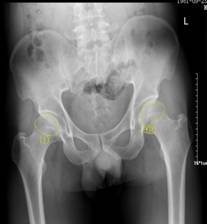

新技术:泸州市中医院成功开展富血小板血浆(PRP)术——早期股骨头坏死患者福音股骨头坏死是一种原因不明的常见骨科疾病,根据不同的发病程度和部位分区有不同的治疗方法。近日,泸州市中医院成功开展的富血小板血浆微创手术(简称:PRP)为早期股骨头坏死患者带来福音,同时也为保髋治疗增添了新的治疗方法。诊断:...